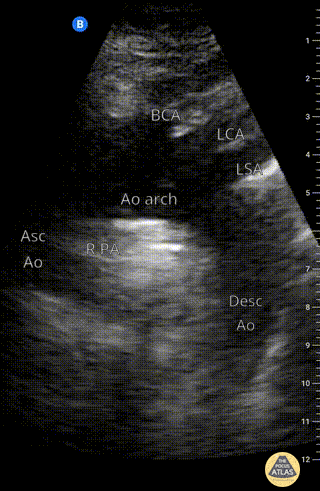

Suprasternal notch view of the aortic arch with brachiocephalic artery (BCA), left common carotid artery (LCA), and left subclavian artery (LSA) branching off. Right pulmonary artery is also visible adjacent to the ascending aorta. Charles Jang, EM PGY-3